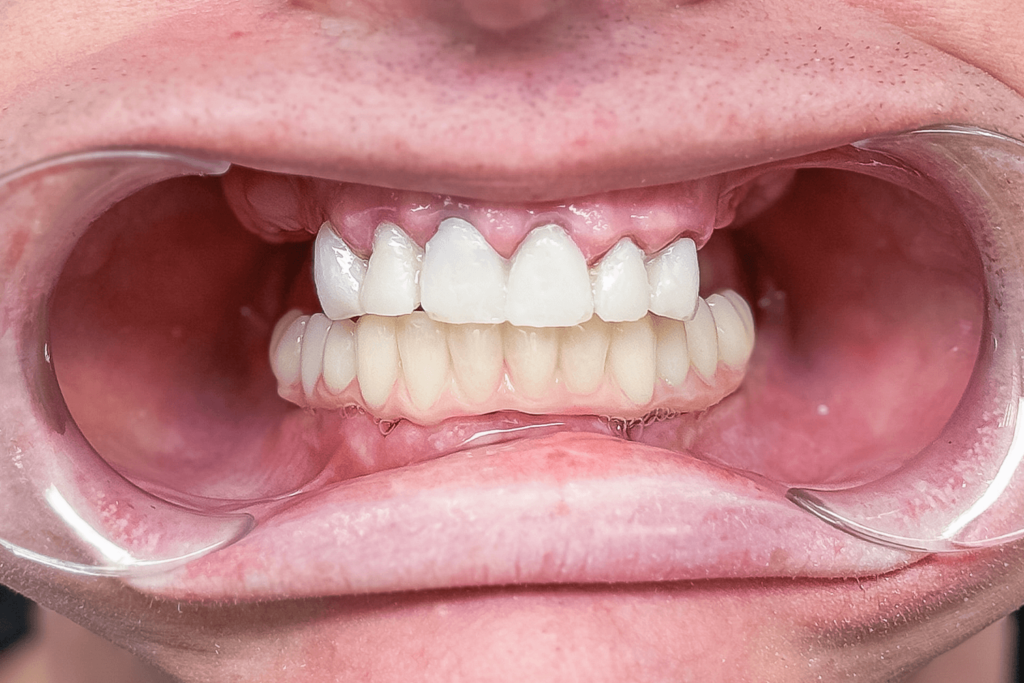

Постоянное протезирование

Через 5 дней пациенту сняли mock-up и приступили к фиксации постоянных ортопедических конструкций. Сделали 2 мостовидных протеза слева и справа на верхней челюсти с винтовой фиксацией и одиночные коронки с цементной фиксацией на зубах 13-23. На нижней челюсти врач зафиксировал сплошной мостовидный протез на фиксации винтовой из 12 единиц, усиленный титановой балкой и назначил дату следующего визита.

Через неделю пациента снова пригласили в клинику на контрольный осмотр. Дополнительно врач провел рентгенологическое исследование, на котором проследил как "села" конструкция и как спозиционировались абатменты в имплантах после нагрузки. Коррекция работы не потребовалась. После этого врач дал рекомендации по уходу, чтобы новые зубы прослужили пациенту как можно дольше: рекомендовалась профессиональная гигиена полости рта дважды в год, использование ирригатора в домашних условиях, контрольный рентген ежегодно.

Итог лечения

В общей сложности лечение длилось 2 месяца и состояло из 7 посещений клиники. Пациенту установили 10 зубных имплантатов Straumann BLT и 24 ортопедические единицы из диоксида циркония в цвете Bleach 2.